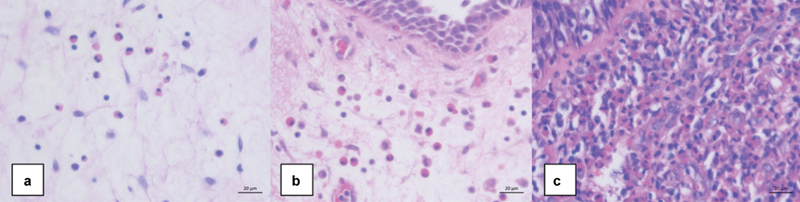

Introduction  Chronic rhinosinusitis with nasal polyposis (CRSwNP) is a chronic inflammatory condition of the paranasal sinuses that is mainly associated with type-2 inflammation. Immunoglobulin E (IgE) and eosinophils in blood and nasal tissue have been suggested as biomarkers for the prognosis and severity of CRSwNP as well as indications for biological treatment. Objective  The present study aims to assess the relationships between blood IgE concentration, blood eosinophil count, and nasal polyp eosinophil count in CRSwNP patients. Methods  The present study is retrospective. Nasal polyps from CRSwNP patients (n = 73) were fixed and embedded in paraffin for hematoxylin and eosin stain. Blood was collected to measure IgE concentration and eosinophil count. Results  Weak correlations were found between blood and tissue eosinophil counts ( p  = 0.004, r = 0.367) as well as blood IgE concentration and blood eosinophil count ( p  = 0.007, r = 0.372). There was no statistically significant correlation between blood IgE concentration and tissue eosinophil count. When dividing patients based on nasal polyp eosinophil count, blood eosinophil level was higher in the severely eosinophilic group than in the mildly eosinophilic group ( p  = 0.002). Conclusion  Blood IgE and eosinophils are not reliable biomarkers to predict the inflammatory condition in CRSwNP. Further research is needed on the clinical roles of these biomarkers.

Abstract Image